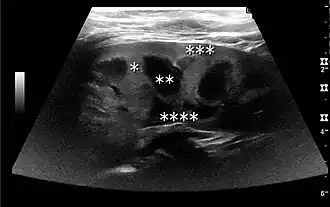

Figure 2. Normal pediatric kidney. * Column of Bertin; ** pyramid; *** cortex; **** sinus.[1] -

The kidney is divided into parenchyma and renal sinus. The renal sinus is hyperechoic and is composed of calyces, the renal pelvis, fat and the major intrarenal vessels. In the normal kidney, the urinary collecting system in the renal sinus is not visible, but it creates a heteroechoic appearance with the interposed fat and vessels. The parenchyma is more hypoechoic and homogenous and is divided into the outermost cortex and the innermost and slightly less echogenic medullary pyramids. Between the pyramids are the cortical infoldings, called columns of Bertin (Figure 1). In the pediatric patient, it is easier to differentiate the hypoechoic medullar pyramids from the more echogenic peripheral zone of the cortex in the parenchyma rim, as well as the columns of Bertin (Figure 2).[1]